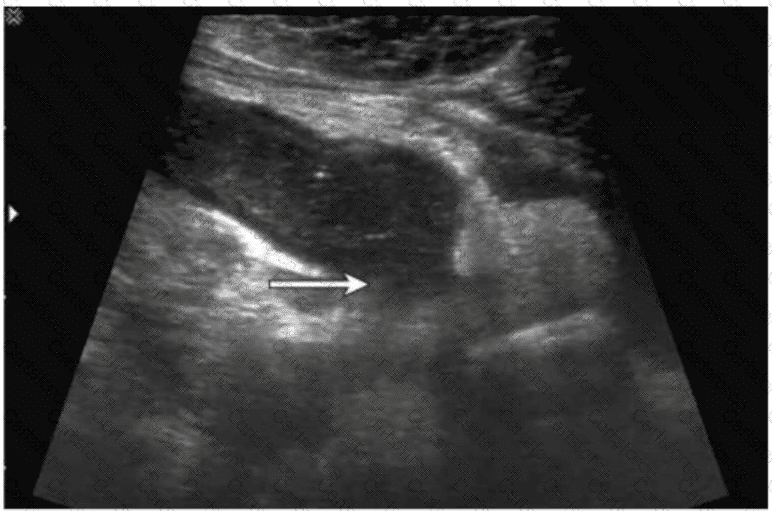

The ultrasound image demonstrates a tubular, non-compressible, blind-ending structure located in the right lower quadrant (RLQ) with associated echogenic periappendiceal fat and possibly adjacent fluid or phlegmon. These features are consistent with appendicitis. Given the clinical history of fever and RLQ pain, along with the irregular borders and complex periappendiceal findings, the diagnosis of a ruptured appendix is most likely.

Key sonographic features of ruptured appendicitis include:

Non-visualization or distortion of the normal appendiceal wall architecture

Periappendiceal fluid collection or abscess

Disruption of the echogenic submucosal layer

Surrounding fat stranding (hyperechoic inflammatory changes)

Clinical correlation with fever and peritonitis

D. Ruptured appendix — Correct. The ultrasound features and clinical presentation match.